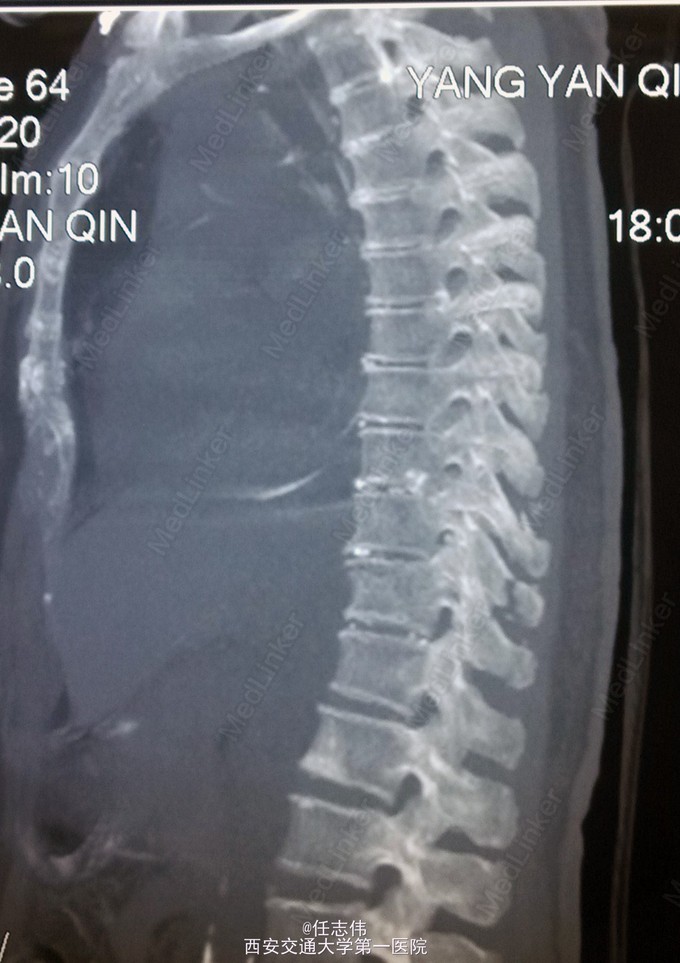

患者女性,60岁,车祸伤致双下肢感觉活动不能8h入院。 8小时前坐农用车时,被横杆撞倒腰部,摔下后感觉胸背部疼痛,双下肢活动不能,伴有短暂昏迷病史。遂来我院就诊。

诊断:1.胸11椎体骨折伴截瘫(Frankel A级)2.闭合性胸部损伤,肺挫伤,多发肋骨骨折,双侧胸腔积液 处理:1.急诊入院告病危,心电血氧监护;2.予以甲强龙冲击治疗;3.次日复查胸部CT,查看肺部损伤情况及胸腔积液,后予以右侧放置闭式引流。患者氧合不稳定,2日后复查胸片胸腔积液减少,予以行后路减压内固定融合术。 手术:术中见局部软组织损伤严重,胸11-12棘上、棘间韧带断裂,胸10、11、12双侧关节突有骨折移位,胸11椎板骨折,胸11左侧不能置入椎弓根螺钉,遂行单纯固定。脊髓局部挫伤明显,并有硬膜破损,予以处理。

术后患者逐渐病情平稳,拔出闭式引流。伤口愈合好。 查体双下肢深感觉有恢复,但肌力仍0级,巴氏征阳性。 1.在没有CT检查时,此骨折容易漏诊,需要注意询问病史,完善检查,尤其是无神经损伤表现者。 2.此患者固定范围应该扩大到腰1吗?还是至胸12就可以了,病椎大家一般都固定吗? 3.对于此例患者大家都急诊手术吗?还是要先处理肺部情况。